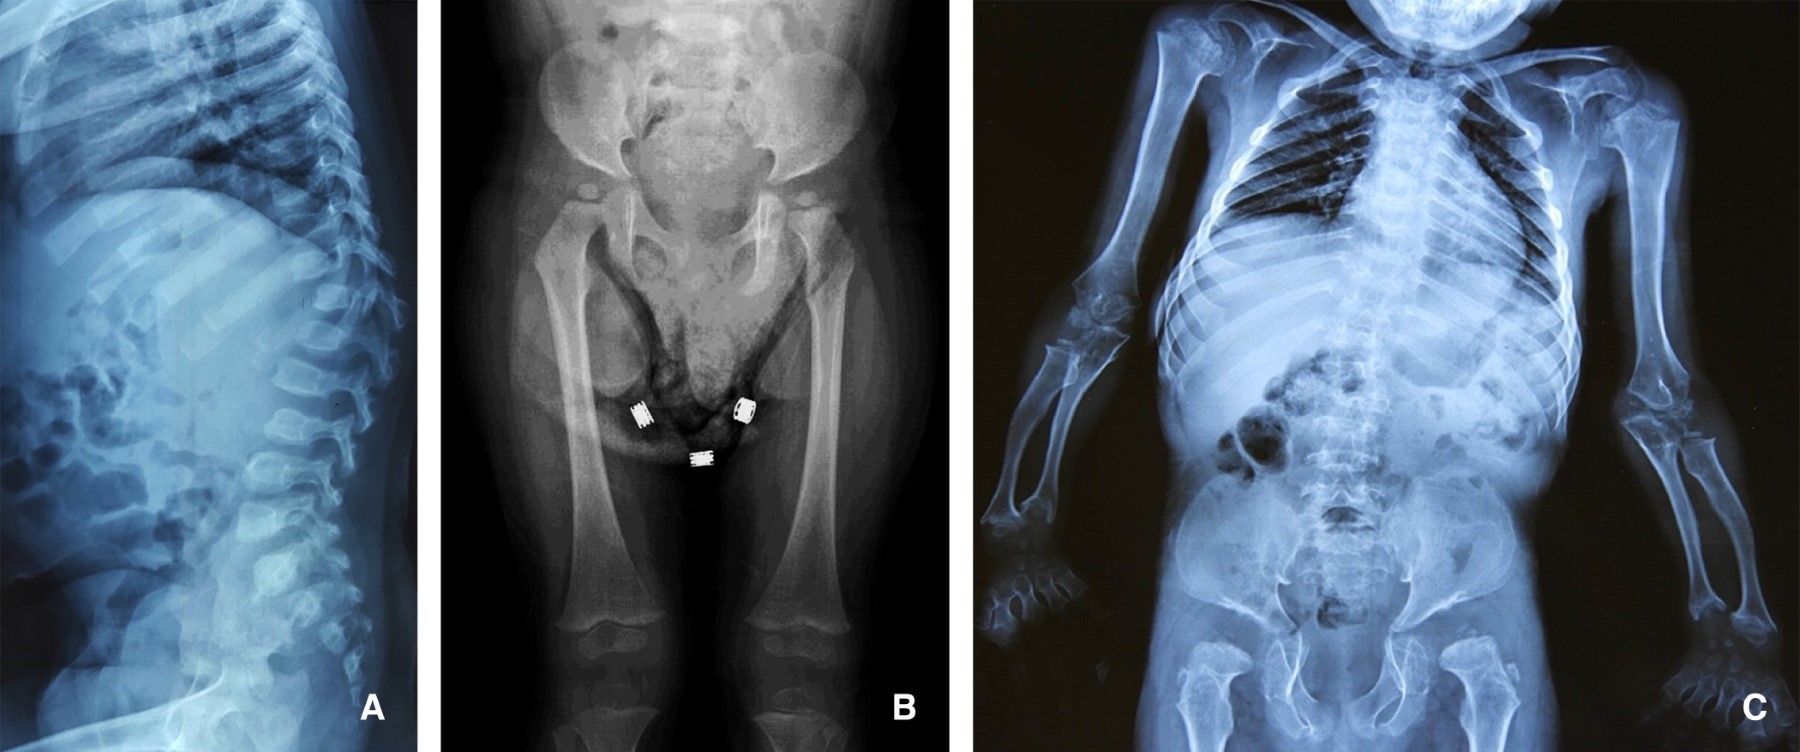

Mucopolysaccharidosis. What the pediatric orthopedist should know

Mucopolysaccharidoses (MPS) are multisystem lysosomal disorders with an estimated incidence of 1 in 25,000 births, characterized by the progressive deposition of glycosaminoglycans (GAGs) that cause cellular and tissue damage. Although diagnosis has improved with biochemical profiles and genetic sequencing, 60-70% of cases are first identified by musculoskeletal manifestations, placing the pediatric orthopedist in a leading role for early detection. MPS present a phenotypic spectrum classified as: 1) hurlerian (MPS I, II, VI) with multiple dysostosis and joint contractures; 2) neurological (MPS III) with psychomotor regression; and 3) skeletal (MPS IVA) with disproportionate short stature and cervical instability. The accumulation of specific GAGs (dermatan/heparan sulfate) determines clinical manifestations, ranging from corneal opacity to spinal cord compression due to odontoid hypoplasia. The orthopedist must recognize key signs such as thoracolumbar hump (pathognomonic in MPS I/IV), progressive genu valgum (> 15°), and irregular femoral epiphyses (mimicking bilateral Perthes syndrome in MPS IVA). Although enzyme replacement therapies have improved survival, orthopedic complications (scoliosis, arthropathy) persist, requiring surgical management (cervical arthrodesis, osteotomies) and multidisciplinary follow-up. This review emphasizes the essential knowledge for the timely diagnosis and comprehensive management of MPS, to optimize the quality of life of these patients.

Figure 1